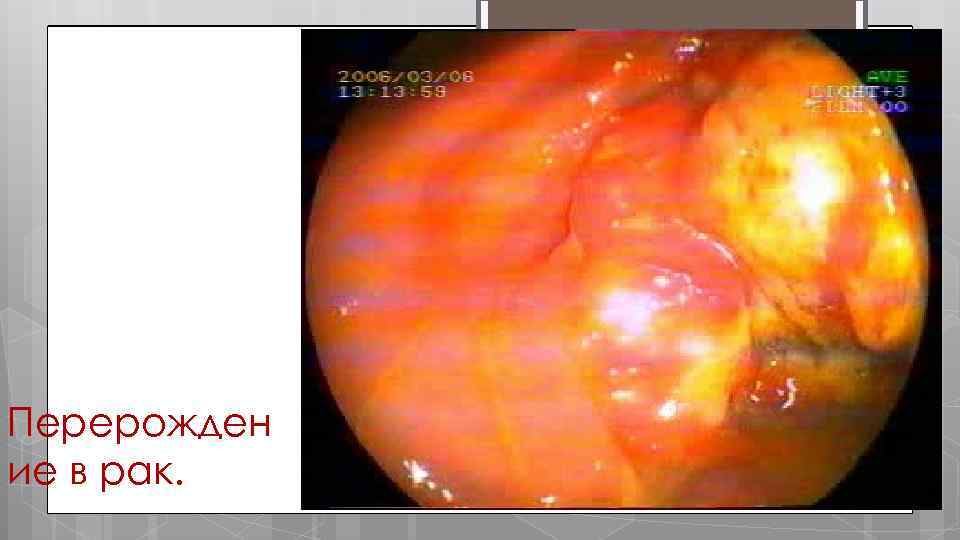

ОСЛОЖНЕНИЯ НЯК ректальное кровотечение острая токсическая дилятация перфорация стеноз псевдополипоз перерождение в рак

Перерожден ие в рак.

На изображении эндоскопический снимок опухоли.